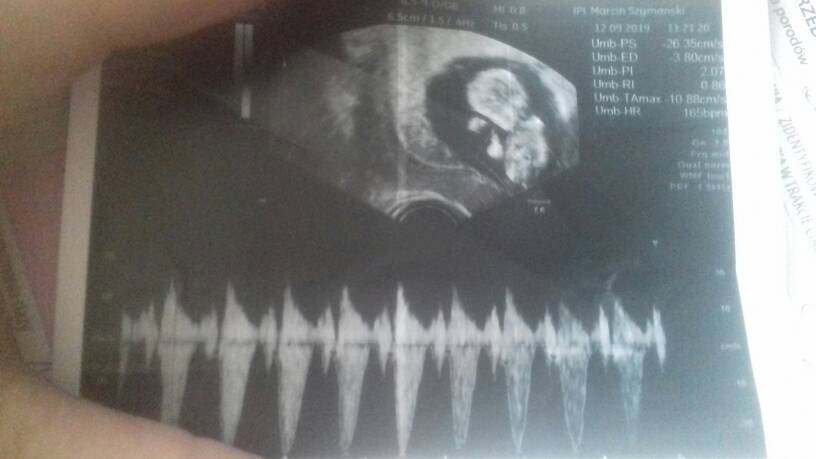

Maluszek ma 47cm 11t3d, serduszko bije 165bpm.

Przeziornosc karkowa 1.34 mm

Kość kosowa 1.27mm

Przeplywy wporzadku.

Nie zalecił żadbych dodatkowych badan gdyż ciąża rozwija sie prawidłowo[emoji5]Zobacz załącznik 1021645Zobacz załącznik 1021646Zobacz załącznik 1021647Zobacz załącznik 1021648